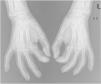

A 50-year-old woman with limited SSc, evolving over 19-years, referred stiffness, pain and ulceration on the first four digital pulps of each hand for one year. She underwent surgical excision of calcium deposits of the 2nd and 3rd fingers bilaterally and started diltiazem 90 mg/day. For two years, there was symptomatic progression. Skin involvement also included sclerodactyly and malar cutaneous telangiectasia. In addition, her SSc was complicated by oesophageal dysmotility, partially controlled with proton pump inhibitors, and severe Raynaud phenomenon (RF), under bosentan. No evidence of pulmonary arterial hypertension or other systemic involvement. Laboratory tests were positive for Antinuclear antibodies (ANA) and anticentromere antibodies (ACA). Physical examination revealed painful, stiff, skin-coloured papules, 4‒10 mm, distributed on the pulp of the 1st, 2nd and 4th right fingers and the 1st left finger, compatible with CC (Fig. 1), as confirmed by hand radiography (Fig. 2). Intralesional STS treatment was proposed due to significant morbidity, progression under diltiazem and the involved site. The procedure was performed using an aseptic technique and under digital nerve block, with a 250 mg/mL solution. Depending on the size of the lesion and pulp distensibility, 0.1‒1 mL of STS solution was injected into the base of the calcifications. Initially, at a 6 to 8-week interval, and after improvement, every 3-months. 25 sessions were performed in 5-years, with continuous symptomatic improvement and better functional status. Hand radiography confirmed a sustained reduction in calcification size (Fig. 3). During the first 2-years, episodes of ulceration and spontaneous drainage of liquified calcium deposits were reported, both self-limited. Additionally, 2 local infections were treated with oral antibiotics. There were no systemic adverse events or analytical abnormalities. However, 2 weeks after the last administration, the patient developed necrosis on the pulp of the 1st right and 2nd left fingers. Treatment with bosentan was suspended 3-months earlier due to long-term control of RF. Oedema from STS infiltration may have triggered a more pronounced RF episode, leading to pulp necrosis. The patient underwent treatment with iloprost 0.4 ng/Kg/min for 3-days and resumed bosentan, with complete healing. Currently, she is asymptomatic, with residual calcifications in hand radiography.